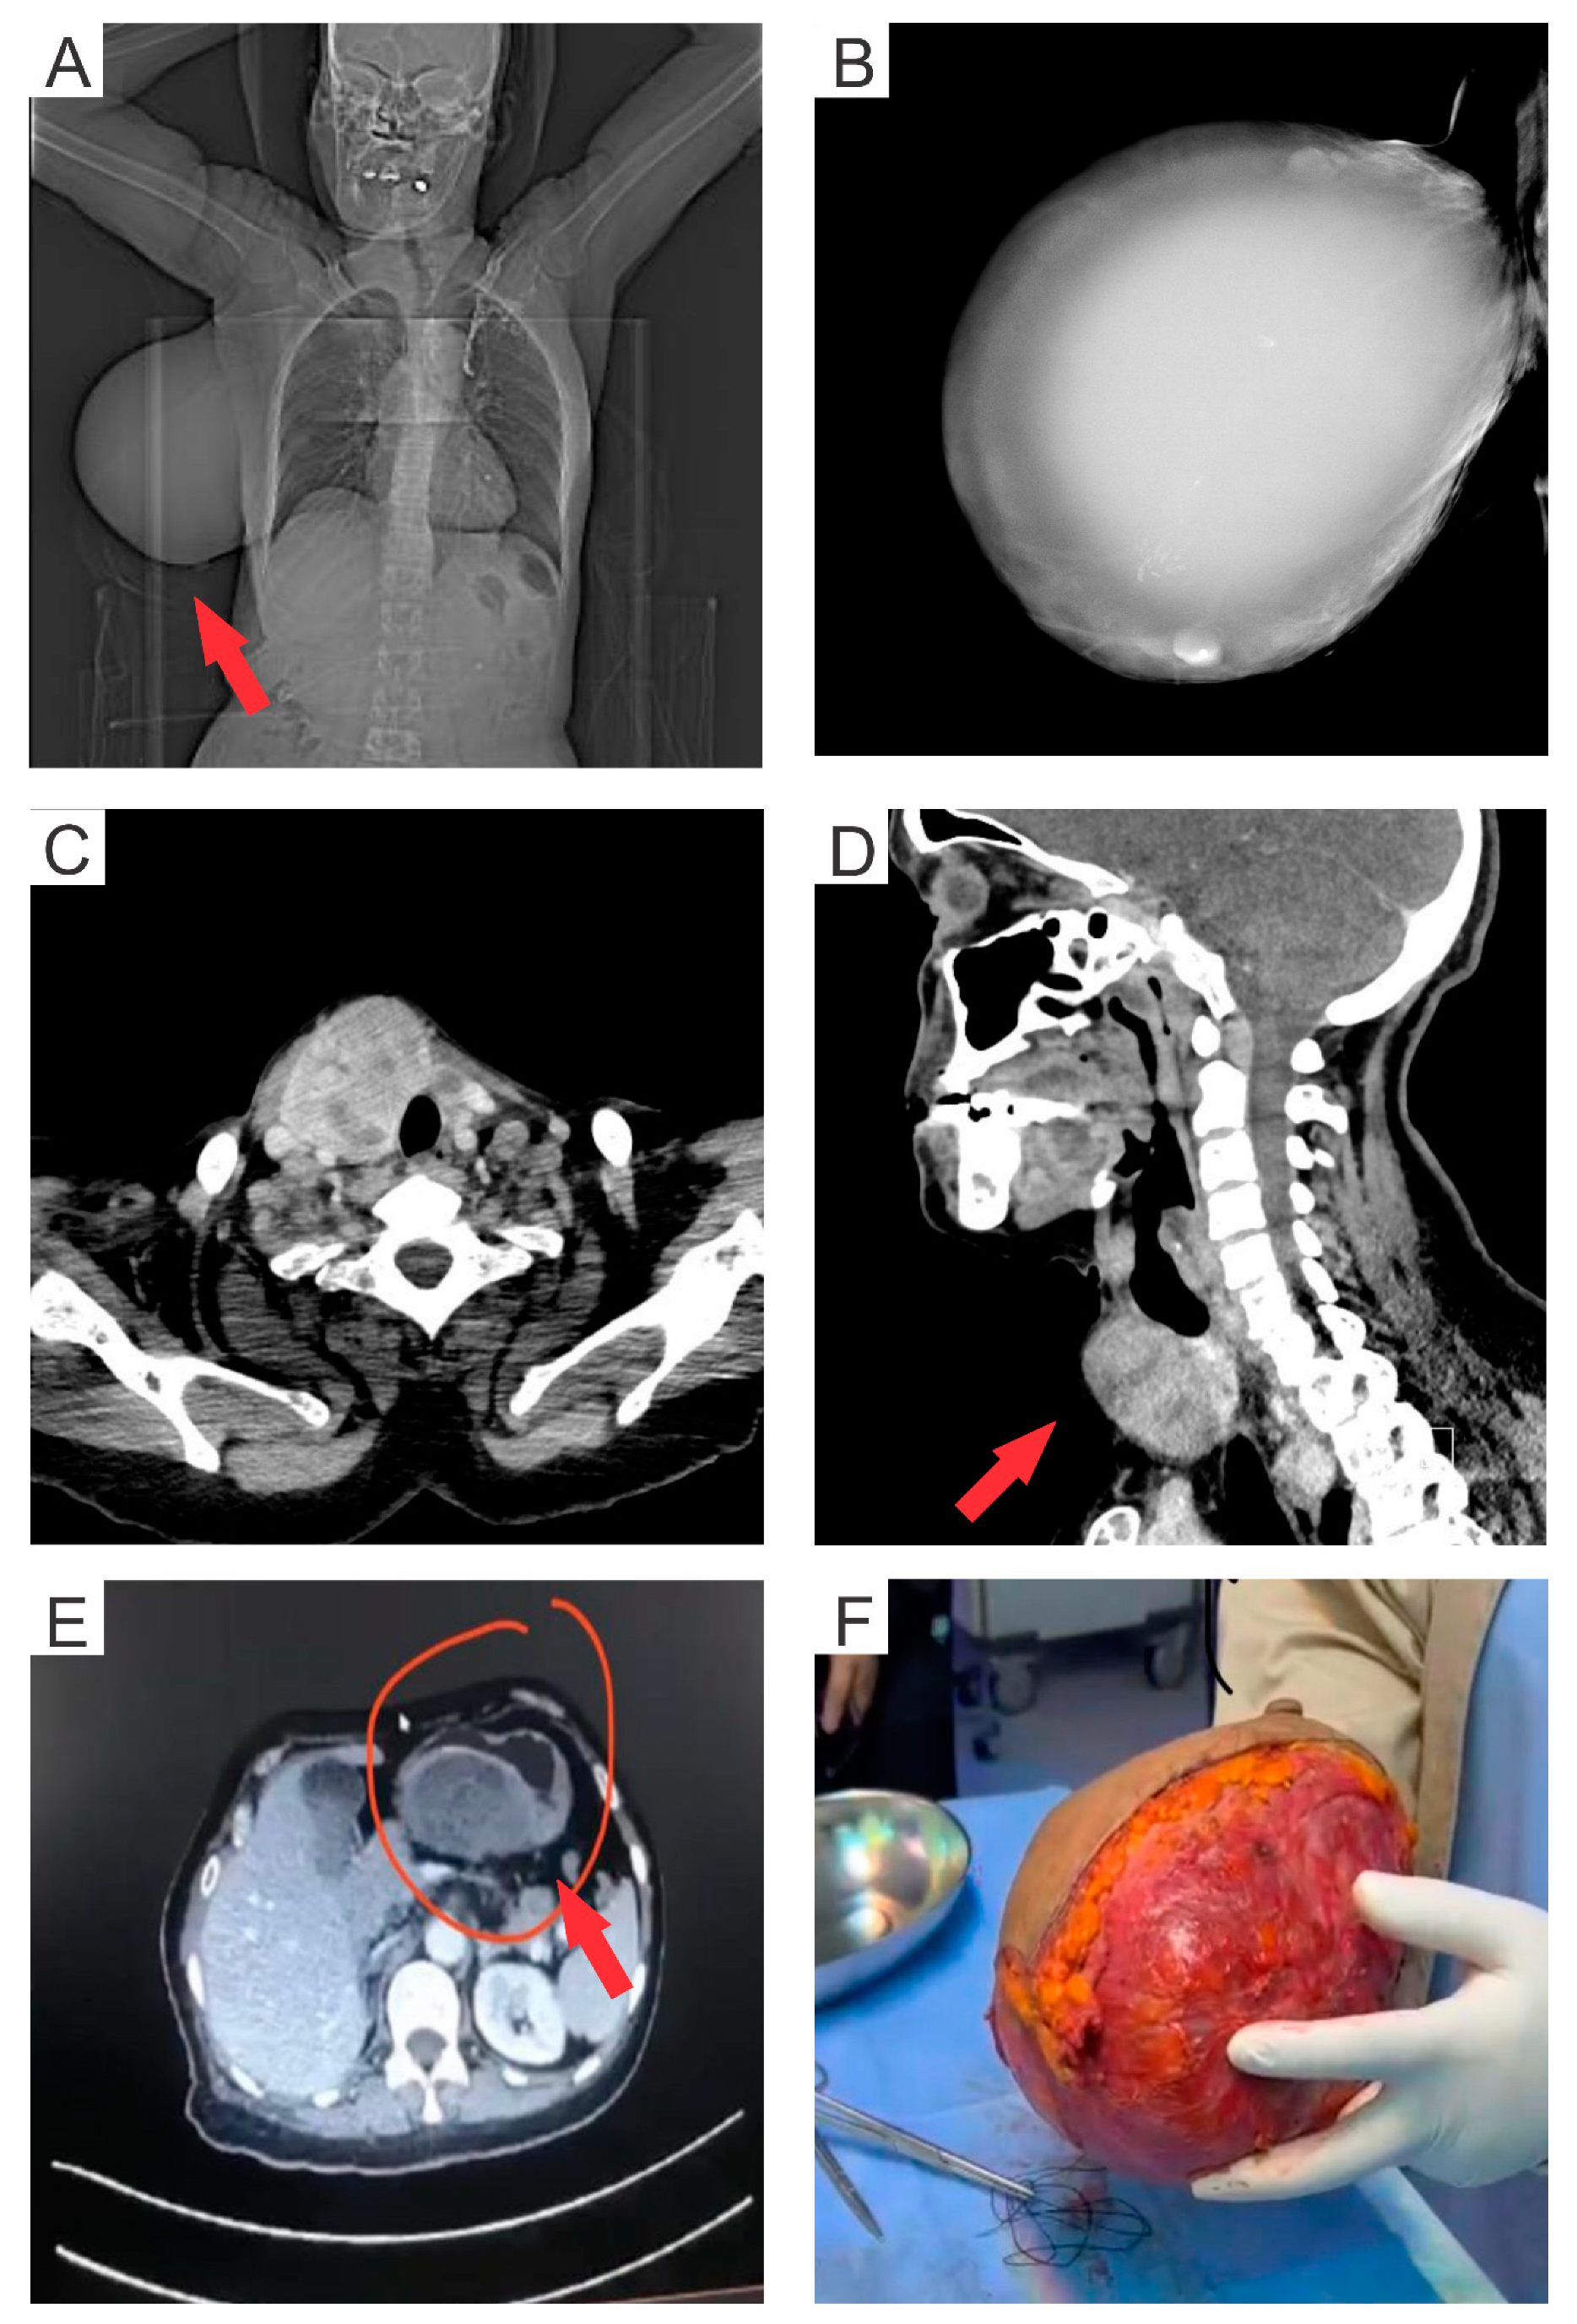

2. Case Presentation

| Present study | 2023 | 56 | Saudi | Coexistence of benign AME with DCIS and spindle cell-type GIST | Adjuvant therapy with total gastrectomy and mastectomy |